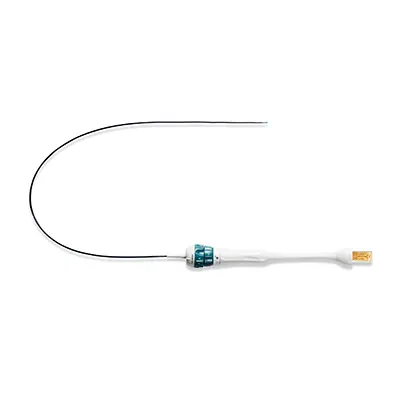

Чреспищеводные датчики используются в кардиологии для получения высококачественных изображений сердца в динамике в различных проекциях. Вводятся в грудную клетку пациента через пищевод. Датчик внешне и по управлению похож на гастрофиброскоп — имеет гибкую рабочую часть и гибкий дистальный кончик. Датчики различаются рабочей длиной, диаметром вводимой части и диаметром дистального кончика. Такие датчики требуют специальной дезинфекции и хранения, бережного обращения.

Датчики, совмещающие в себе видеогастрофиброскоп или видеобронхофиброскоп и ультразвук, называются EUS (Endoscopic Ultrasound) или эндоскопический ультразвук. По типу излучателя бывают конвексные, микроковексные и радиальные (с 360-градусным обзором). Являются примером мультимодального получения изображения, когда на одном экране отображается изображение с двух разнородных систем визуализации — с ультразвука и видео с эндоскопа.